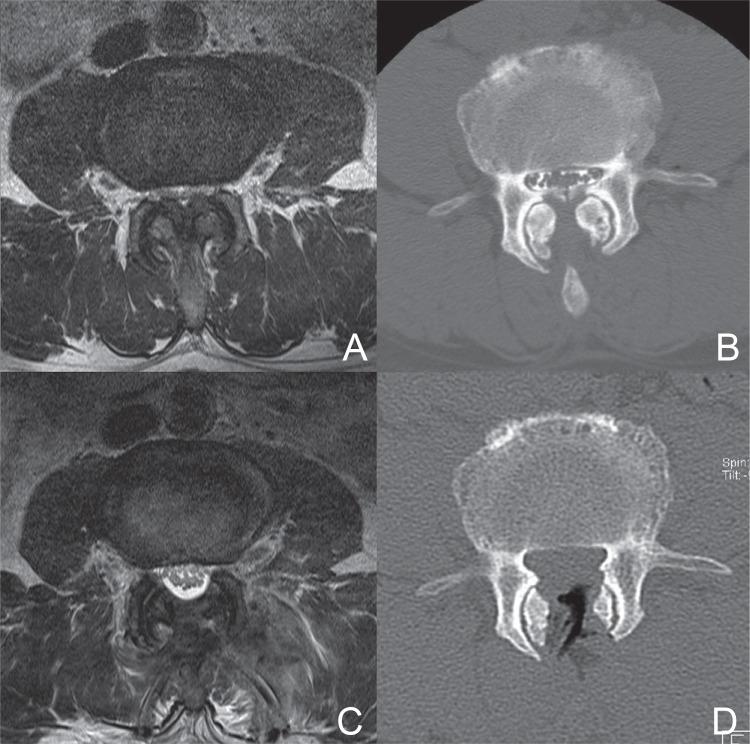

The purpose of this study was to determine the feasibility and efficacy of bilateral decompression procedure via microscopic tubular crossing laminotomy (MTCL) for treating lumbar spinal stenosis (LSS). Seventeen patients with LSS underwent bilateral decompression via an MTCL procedure in which tubular retractor was placed. The mean age was 72 (range 59-84) years and there were 10 men and 7 women. All patients underwent pre- and postoperative dynamic lumbar x-ray, magnetic resonance (MR) image, and computed tomography. To verify the efficacy of this technique, pre- and postoperative cross-sectional area (CSA) of thecal sac, facet resection, and fatty infiltration (FI) of multifidus were measured. Clinical results were evaluated using Oswestry Disability Index (ODI), back and leg visual analog scale (VAS). The mean follow-up period was 17.5 months (range 12.1-21.2). 70.5% of MTCL was performed at the level of L4-5 and one case of dural violation (5.8%) was noted at the level of L5-S1. The mean preoperative CSA was 70.5 mm(2) (range 25.1-87.6) and it increased to 198.8 mm(2) (range 177.3-219.2) postoperatively (p = 0.00). The mean facet resection rate was 18.4% (range 9.9-26.9) and no radiological instability was noted postoperatively. MR image showed no increase in FI of the multifidus after 12 months of follow-up (p = 0.53). Preoperative clinical symptoms improved significantly at postoperative 6 months and 12 months of follow-up. These results indicate that an MTCL with use of tubular retractor system can be an effective procedure to achieve neural decompression for the treatment of LSS and it may be beneficial in preserving both facet joint and multifidus muscle.

本研究旨在确定经显微管状交叉椎板切开术(MTCL)行双侧减压治疗腰椎管狭窄症(LSS)的可行性和疗效。17例LSS患者接受了经MTCL双侧减压手术,术中放置了管状牵开器。平均年龄为72岁(范围59 - 84岁),男性10例,女性7例。所有患者均接受了术前和术后动态腰椎X线、磁共振(MR)成像及计算机断层扫描。为验证该技术的疗效,测量了术前和术后硬脊膜囊的横截面积(CSA)、关节突切除情况以及多裂肌的脂肪浸润(FI)。使用Oswestry功能障碍指数(ODI)、腰背部和腿部视觉模拟量表(VAS)评估临床结果。平均随访期为17.5个月(范围12.1 - 21.2个月)。70.5%的MTCL手术在L4 - 5节段进行,在L5 - S1节段有1例出现硬脊膜损伤(5.8%)。术前平均CSA为70.5 mm²(范围25.1 - 87.6),术后增加至198.8 mm²(范围177.3 - 219.2)(p = 0.00)。平均关节突切除率为18.4%(范围9.9 - 26.9),术后未发现影像学不稳定。随访12个月后,MR图像显示多裂肌的FI无增加(p = 0.53)。术前临床症状在术后6个月和12个月的随访中显著改善。这些结果表明,使用管状牵开器系统的MTCL可能是一种有效的神经减压手术,可用于治疗LSS,并且可能有助于保留关节突关节和多裂肌。